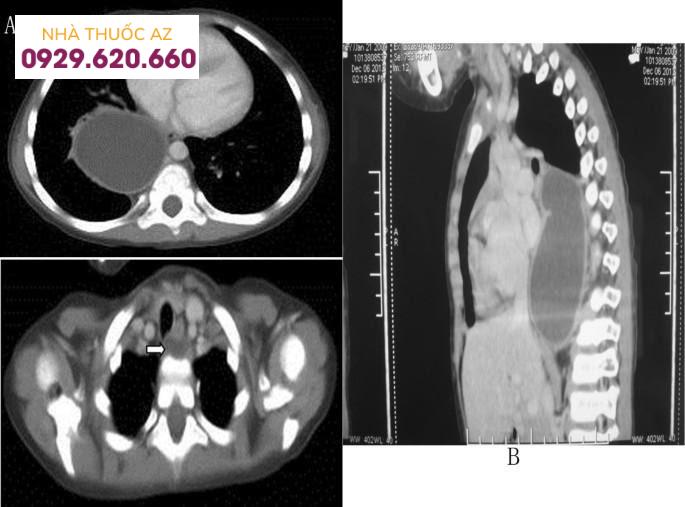

Hình 3: Hình ảnh chụp cắt lớp vi tính của một bệnh nhi nam, 3 tuổi, tiền sử khỏe mạnh, có biểu hiện sốt cấp tính từng cơn và ho khan, nhưng không khó nuốt, sốt (39,0 ° C). Chụp cắt lớp vi tính (Chụp cắt lớp vi tính) khi thăm khám ban đầu cho thấy một khối u trung thất lớn ở lồng ngực, có biến chứng viêm phổi. Việc tái tạo Chụp cắt lớp vi tính ba chiều đã cho thấy rằng hai khối u nang hình bầu dục nằm ở trung thất sau, có ranh giới rõ ràng và chứa đầy chất lỏng, nhưng không có bất kỳ mức dịch khí nào. U nang lớn hơn có kích thước 10 cm x 5,4 cm x 5,8 cm. Nó nằm ở phần giữa và phần dưới của thực quản trong khoang cạnh sống và kéo dài dọc theo rãnh đốt sống bên phải. U nang đẩy lệch khí quản phía trước, phế quản chính bên phải và thùy dưới bên phải phổi ở phía trước. U nang nhỏ hơn nằm giữa thành sau của thực quản cổ, với kích thước 1,0 cm × 0,8 cm. Chụp cắt lớp vi tính Scan cản quang không cho thấy bất kỳ sự tăng quang rõ ràng nào của cả hai u nang. Bệnh nhân được chẩn đoán bệnh nhân được chẩn đoán là nang thực quản có biến chứng viêm phế quản phổi.